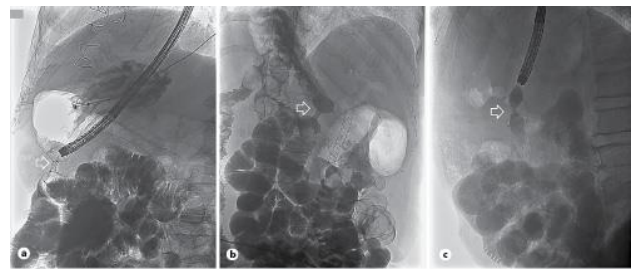

Fig. 3: Fluoroscopic confirmation of LAMS correct placement (arrows) in patient 1 (a), 2 (b), and 3 (c).

Case 2: 78-year-old female patient with pancreatic ductal adenocarcinoma of the uncinate process, locally advanced with mesenteric vessels involvement. She presented with obstructive jaundice and underwent an endoscopic retrograde cholangiopancreatography with successful placement of metal biliary stent. Patient refused any neoadjuvant chemotherapy and six weeks later, she developed GOO symptoms and stricturing tumoral infiltration of the distal second portion of the duodenum [5-6]. After multidisciplinary discussion, she was proposed for EUS-GJ. Procedure was performed with a 20 mm × 10-mm LAMS through the posterior gastric wall using WEST [7]. Patient has a successful 6 months period of food tolerance after which she passed away from the progression of her disease.

The procedure involved instilling 900 cc of saline solution with methylene blue to promote jejunal dilation using a catheter. Under ultrasonographic guidance, the bowel loop was accessed using a "wireless endoscopic simplified technique" (WEST), placing a lumen-apposing stent (LAMS) through the greater curvature of the stomach. The enteral communication was created and dilated with a through-the-scope balloon up to 15 mm .[3-4]. The patient restarted oral food intake within 12 hours and remained food-tolerant until he passed away, 3 months after the procedure